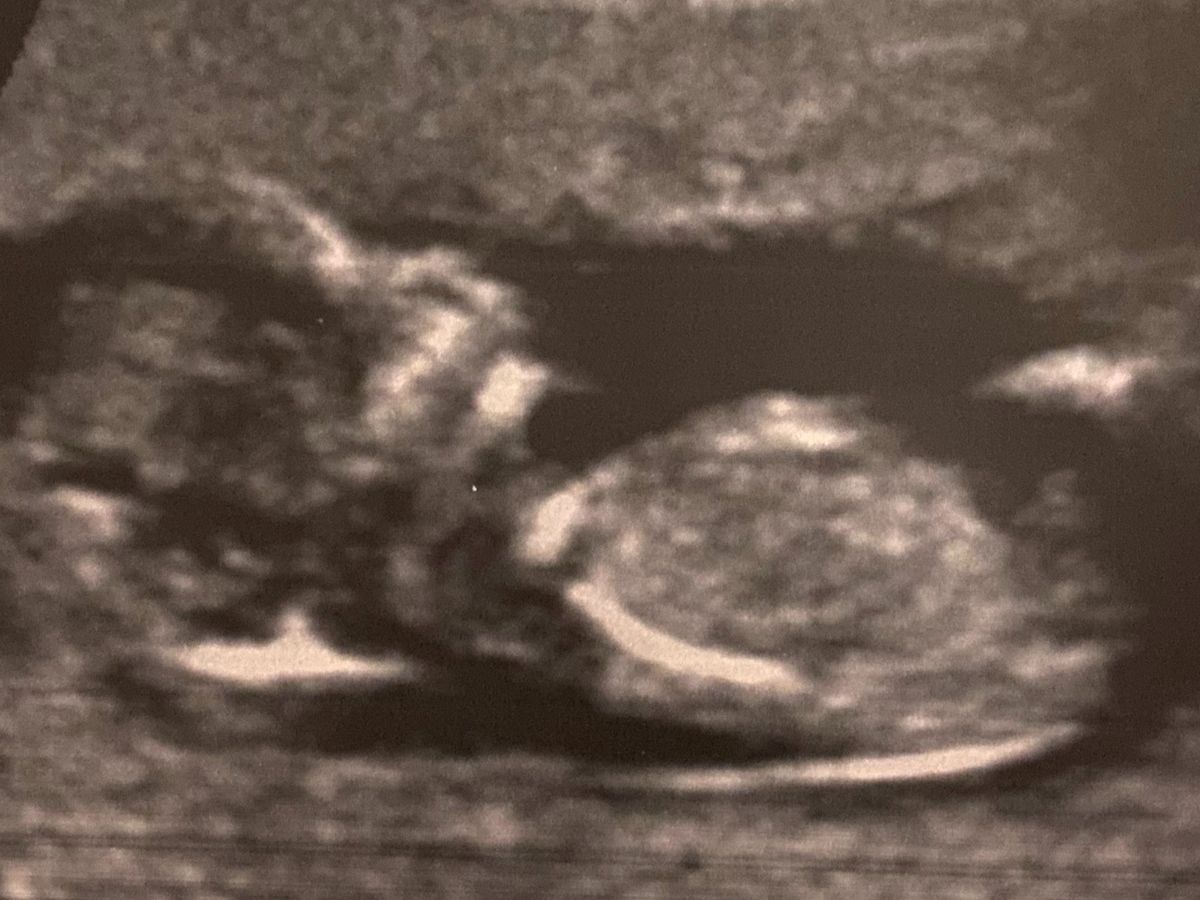

So as many know our baby Theo was given zero chance of survival. He has no amniotic fluid, which means he can not develop lungs. Today at our ultrasound we learned that this is due to Theo not having kidneys. I was offered to go to Standford University in California for a extended stay, have fluid added to my amniotic sack, allow Theo to grow and then when born he will be given part of my kidney or if needed the closest match. Then if all was successful we would come home. There is a lot of what if’s, and with out this there is still zero chance. It appears Theo is perfectly healthy otherwise and is growing perfectly on track. This is not a guarantee that we will get to bring him home but it’s our only chance to try. They are showing a lot of success with this trial. The part we are facing is our out of pocket co pay, and then travel expenses. Housing, food and some gas will be covered by the trial. Brandon will stay home and the kids and I will go, I have some family that is somewhat local as well as friends to the San Francisco area along with our own family that can travel down occasionally. As many know we are a big family on a single income. There is a financial aspect to this standing in the way. The minimum needed for co pay and first round of travel expenses is just shy of $10,000 after that it will just be a very long stay for the kids and I but they will cover housing and we can make it work! It was suggested I start a go fund me & lots of prayers. Theo has been given zero chance for a long time now, and now he has a chance and we want to try and take it. We appreciate any and all support through prayer, meals, visits and emotional support.